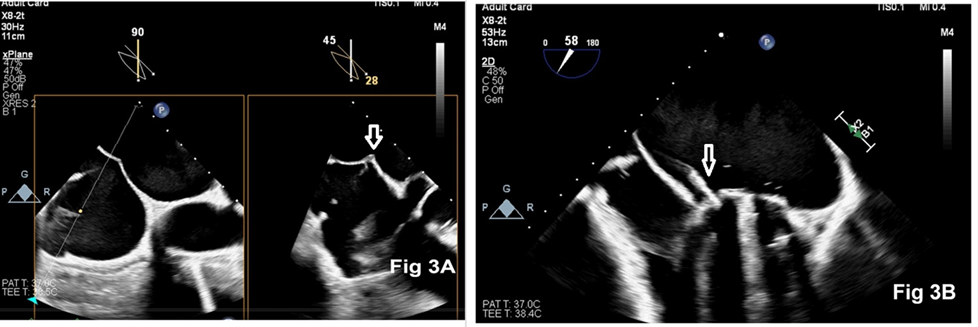

transcatheter closure of the PVLs to the patient and, informed consent was obtained. Considering the complexity and duration of the procedure, along with the requirement of intraoperative TEE, the procedure was performed under general anaesthesia in a hybrid operating room. En-face view of the mitral valve showed severe PVLs through 3 defects: two at the 2 o’clock position and one at the 7 o’clock position (Figure 2A, 2B). Antegrade trans-septal approach via the femoral vein was chosen for PVL closure (Fig 3A). A telescoping coaxial system was introduced into the LA, including a trans-septal LA sheath. An 8.5 F Agilis NXT Steerable introducer, a 6 F coronary guide (multipurpose catheter), and a 5 Fr multipurpose diagnostic catheter were used during the procedure (Figure 3B). Fluoroscopy with RT-3D TEE was used for the successful insertion of the guide wire through the defects. All three PVLs were closed successfully with AmplatzerTM Vascular Plug II devices in a stepwise manner (Figure 4A, 4B, 4C). At the end of the procedure, there was no residual PVL (Fig 4D). The patient made an uneventful recovery.

Figure 3: Two-dimensional echocardiography showing trans-septal puncture (Fig 3A) and a steerable introducer sheath positioned at the paravalvular leak (Fig 3B)